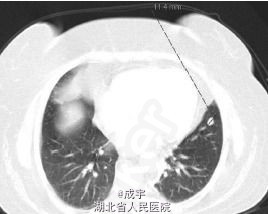

体检:病人呈Cushing’s 综合征表现,满月脸、皮肤毛细血管扩张、皮肤萎缩、水牛背、腹及上肢紫纹、远端肌肉萎缩和外周水肿。血压:158/90mmHg。 辅助检查:检查显示高胆固醇血症、空腹血糖增高、糖化血红蛋白5.2%、低钾,无其它电解质紊乱,无肾功不全。 连续2天尿游离皮质醇明显增高,晨血ACTH和皮质醇明显增高,无ACTH/皮质醇正常昼夜节律,无论是高还是低剂量的地塞米松都不能抑制血和尿中的皮质醇,尿中的5羟吲哚乙酸正常。垂体MRI检查未发现异常,双侧岩下窦标本也未显示中央-外周的ACTH梯度。 CRH刺激试验证实存在异位ACTH存在,胸片、支气管镜及灌洗液细胞学检查无阳性发现,肺CT显示左上肺下舌叶有一12mm的小结节(见图2),腹部CT显示肾上腺及其它腹部器官无异常。

诊断:异位cushing's综合征 治疗:病人同意开胸肺叶切除,病理最终证实为不典型类癌,有丝分裂率4 /10 HPF,免疫组化显示ACTH阳性,其它神经内分泌标志如嗜铬蛋白A和突触素也是阳性,但生长抑素受体阴性。术后血浆ACTH和皮质醇降至正常,病人之前的症状也明显缓解。5年后她仍未有复发的表现。